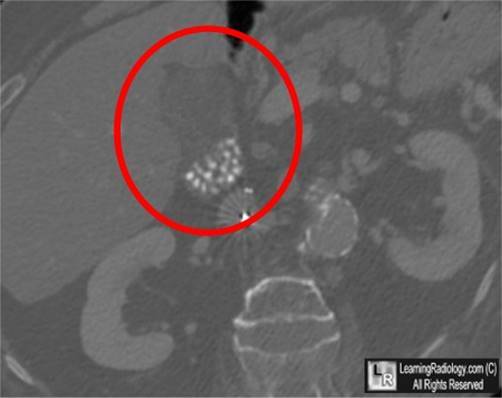

What is shown on this imaging study?

Cholelithiasis